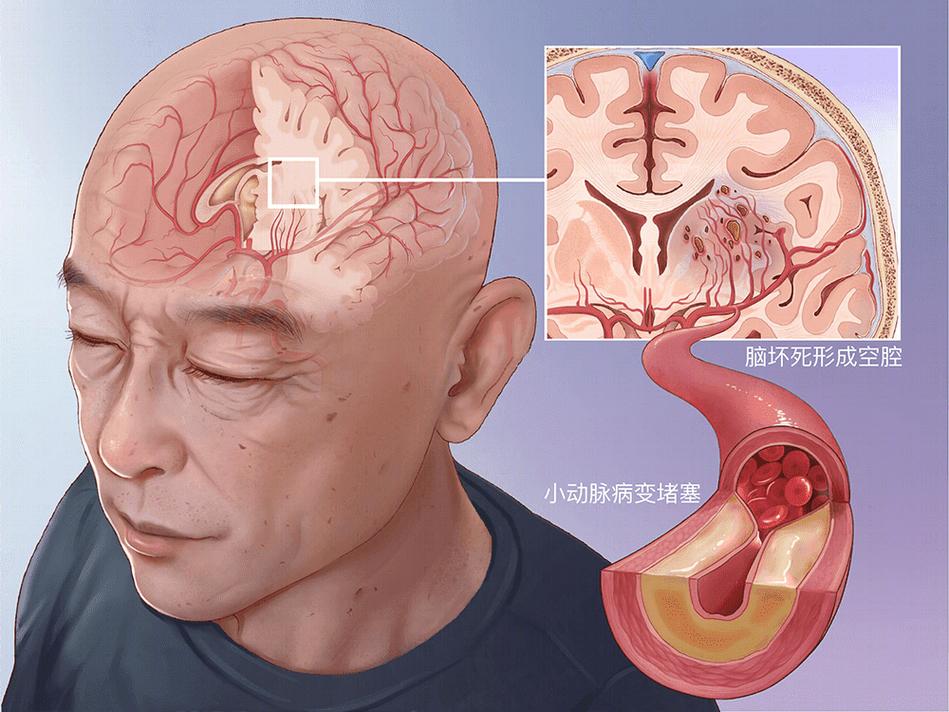

要理解这个问题,我们首先要明白什么是“腔隙性脑梗塞”(简称“腔梗”)。

- 病因:大脑的深部有一些非常细小的穿通动脉,它们负责供应脑深部结构(如基底节、丘脑、脑干等)的血液,这些小血管本身就非常脆弱,长期高血压、糖尿病、高血脂等因素会损伤这些血管的内壁,导致血管壁变脆、变窄,甚至形成微小动脉瘤。

- 过程:当这些小血管完全堵塞时,它所供应的那一小块脑组织就会缺血、坏死,形成一个很小的“梗塞灶”,由于这些梗塞灶通常位于脑组织深处,坏死组织被清除后,会留下一个小空腔,所以被称为“腔隙性梗塞”,其影像学表现就是“腔梗灶”。

- 特点:单个腔梗灶通常非常小(直径一般小于1.5厘米),引起的症状可能很轻微,甚至没有任何症状,因此被称为“静息性脑梗塞”或“无症状性脑梗塞”。